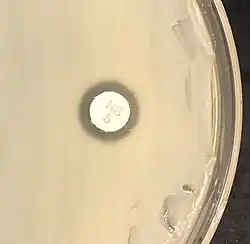

| S. saprophyticus on Mueller–Hinton agar exhibiting resistance to novobiocin characteristic for species identification | |

Staphylococcus saprophyticus is identified as belonging to the genus Staphylococcus using the Gram stain and catalase test. It is identitified as a species of coagulase-negative staphylococci (CoNS) using the coagulase test. Lastly, S. saprophyticus is differentiated from S. epidermidis, another species of pathogenic CoNS, by testing for susceptibility to the antibiotic novobiocin. S. saprophyticus is novobiocin-resistant, whereas S. epidermidis is novobiocin-sensitive.[3]